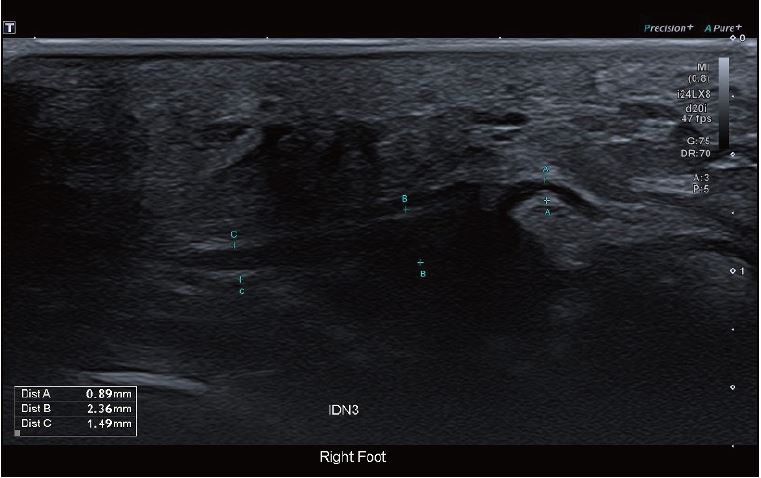

Зображення 2 міжпальцевого нерва показує незначне потовщення невеликої ділянки нерва. У найвужчому місці вона становить 0,9 мм з осередковим потовщенням до 2,4 мм, що вказує на можливу неврому.